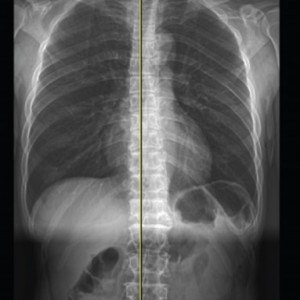

엑스레이 검사

좌우 골반 수평 및 비틀림 측정

흉추, 요추 만곡, 척추 휘어짐 측정

좌우 다리 길이와 틀어짐 측정

엉덩이 관절의 염전각 측정

경골의 회전과 내반 측정